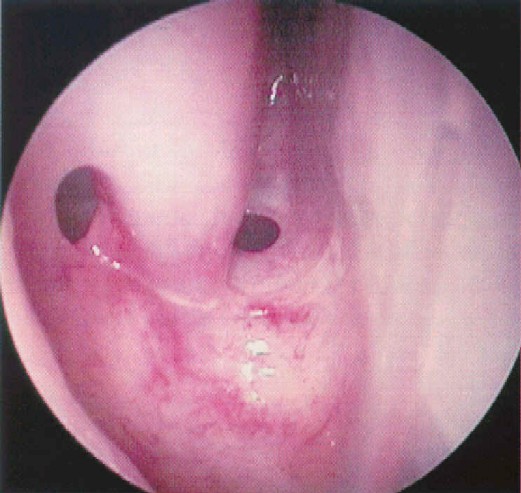

Vista endoscópica de la pared

anterior del seno esfenoidad. |

Cráneo Oseo. Imagen endoscópica del

rostrun del esfenoides observándose lateralmente los ostiun

esfenoidales. |